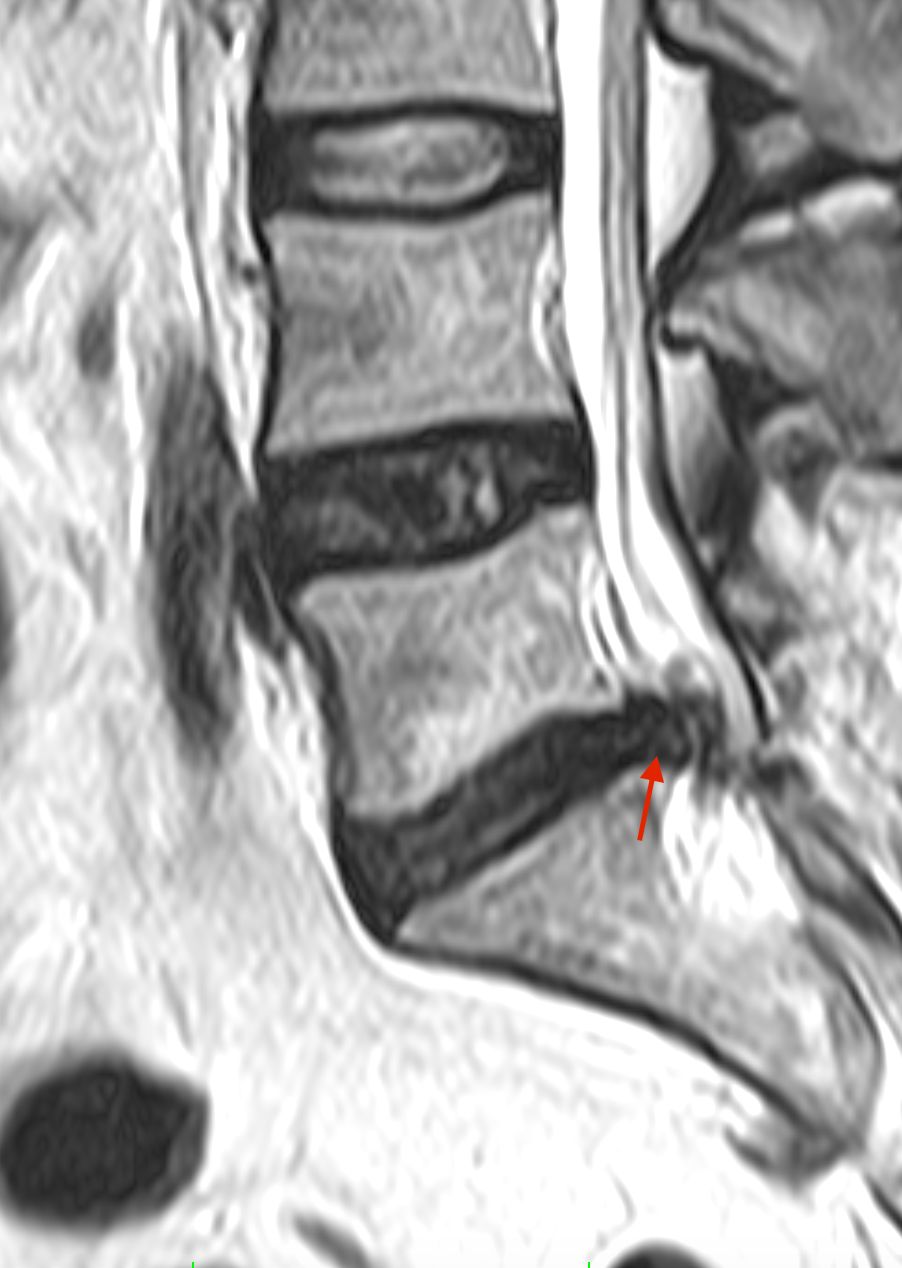

• ernia del disco cervicale, toracica e lombare;

• stenosi del canale vertebrale cervicale e lombare;

• spondilolistesi cervicale e lombare;